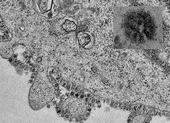

Bảng khuyến cáo ngừa lây lan virus Corona tại một trạm tàu điện ở Bangkok (Thái Lan) ngày 1-2. Ảnh: AFP